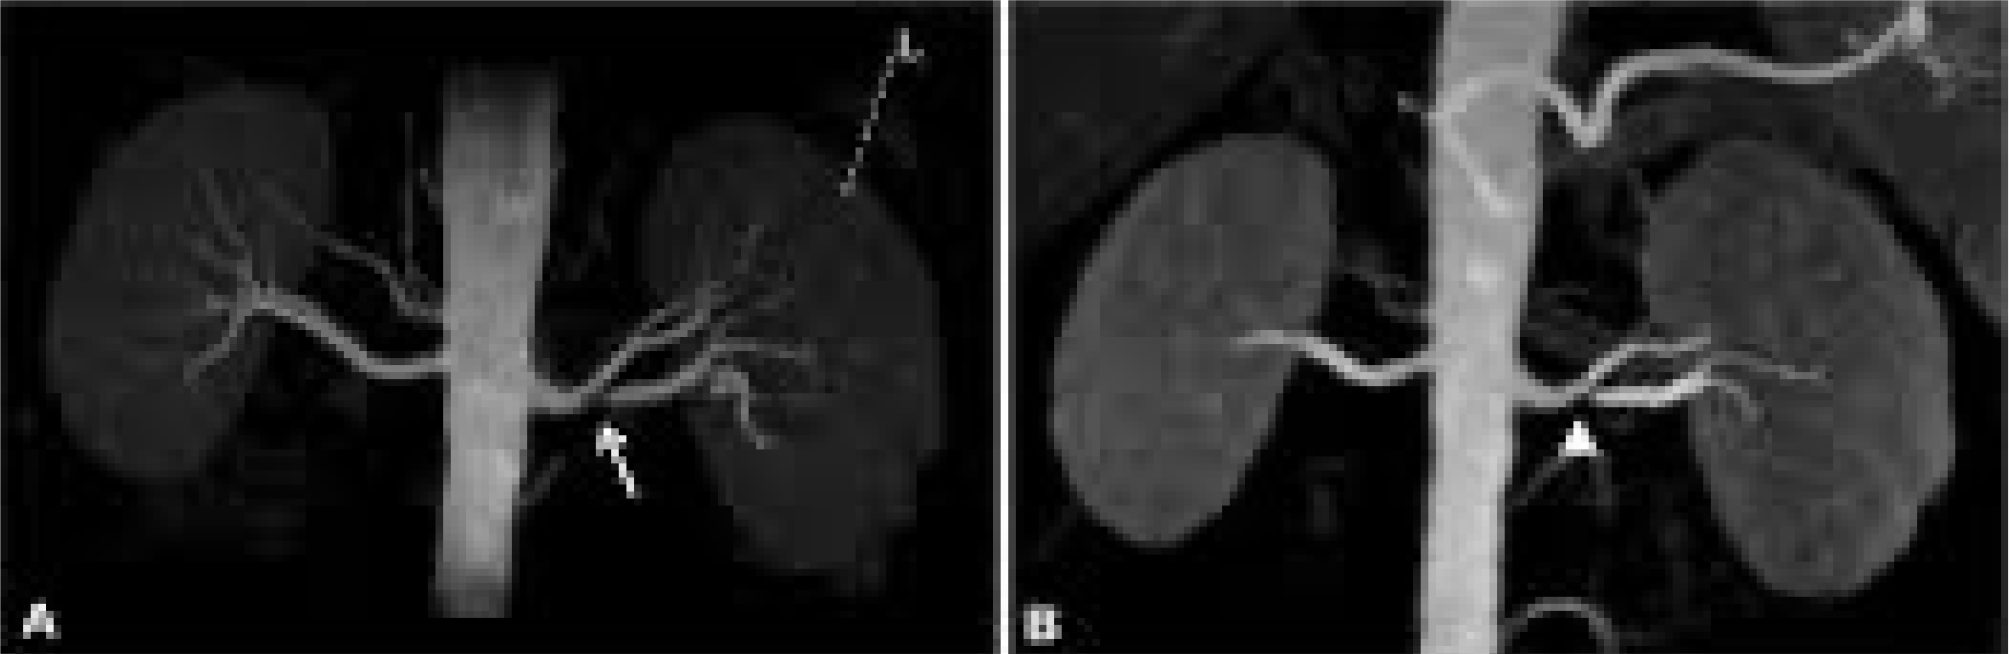

3D Fire

Non-contrast-enhanced (NCE) renal magnetic resonance angiography (MRA) serves as an excellent alternative to the conventional contrast-enhanced approach. This method eliminates the need for ionizing radiation and avoids the injection of gadolinium, a contrast material. The advantages include minimized patient discomfort, reduced examination expenses, and the avoidance of potential risks associated with nephrogenic systemic fibrosis.